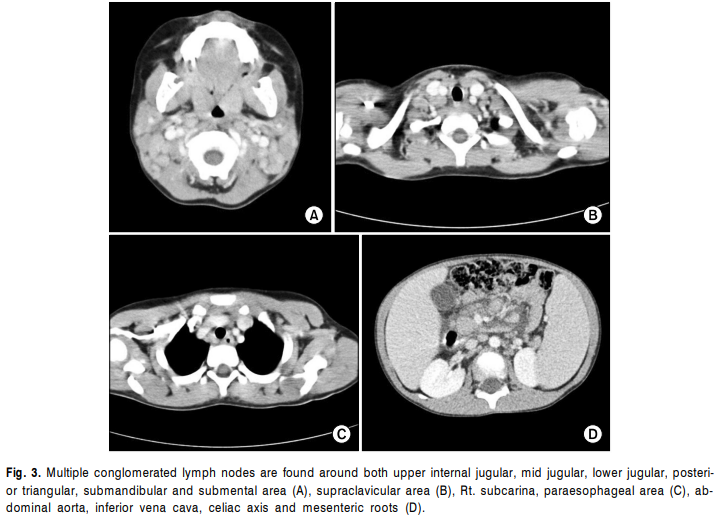

4세에 내원 전일부터 38.4℃까지 오르는 발열을 주소로 입원하여 시행한 말초혈액검사상 혈색소 9.3g/ dL, MCV 55.1fL, MCH 17.3pg, MCHC 31.4g/dL, 백혈구 5,670/mm3 (호중구 59%, 림프구 33%, 단핵구 6%, 호산 구 1%, 비전형림프구 1%), 혈소판 218,000/mm3 이었고, 직접/간접 Coombs’ 검사는 모두 음성이었으며 말초혈 액 도말검사상 저색소성 소적혈구 형태를 보였다. 혈 액화학검사상 AST/ALT 117/65IU/L, 총 빌리루빈 0.40 mg/dL, LDH 712IU/L이었고, C-반응성 단백질은 0.37 mg/dL, 혈청 철은 166μg/dL, 총철결합능은 348μg/dL 이었고, ferritin은 17.5ng/dL이었다. IgG/IgA/IgM 은 각 각 788/52/293mg/dL이었으며, HBs Ag/Ab, HAV IgM, HCV Ab는 모두 음성이었다. EBV IgG, EA (early antigen) IgG, EBNA (EBV nuclear antigen) IgG는 양성이 었으며, 자가 항체 중에서 항핵항체, 루푸스항응고인자, 항카디오리핀항체가 양성이었다. 흉부 단순 방사선검사에서 특이 소견 없었으며 복부 단순 방사선검사에서는 간비비대 소견을 보이고 있었다(Fig. 1). 골수 검사에서는 혈구탐식성림프조직구증의 소견은 보이지 않았으며 적혈구계열이 감소되어 있었다. 경부 림프절 조직검사에서는 림프구증식증과 불규칙한 모양의 과 증식성 여포가 관찰되었으며 많은 수의 림프구들에서 in situ hybridization 방법으로 EBV 감염을 증명할 수 있었다(Fig. 2). 혈액, 골수, 경부 림프절에서 EBV PCR (polymerase chain reaction)은 양성이었으며 흉부, 복부, 경부 전산화 단층촬영에서 다발성 림프절종대 소견이 관찰되었다(Fig. 3). 성염색체연관림프증식증후군과 감별하기 위해 시행한 SLAM(signaling lymphocyte activation molecule)-associated protein(SAP) 유전자 검사에서는 특이 소견 없었다. 환아는 면역글로불린 투여 후 호전되어 8병일에 퇴원하였다.

검사소견: 환아는 내원 당시 말초혈액검사에서 혈색소 10.4g/dL, MCV 57.7fL, MCH 17.9pg, MCHC 31.0g/dL, 백혈구 4,650/mm3(호중구 70%, 림프구 22%, 단핵구 6%, 호산구 1%, 호염기구 1%), 혈소판 205,000/mm3이었고, 화학검사상 AST/ALT 84/50IU/L, 총 빌리루빈 0.27mg/dL, LDH 762IU/L, ferritin 57.8ng/mL, 중성지방 190mg/dL이었다. C-반응성 단백질은 0.95mg/ dL이고 EBV IgG, EA IgG, EBNA IgG, EBV PCR은 양성이었다. 조혈모세포이식을 준비하기 위하여 시행한 심장 초음파 검사에서 좌우 관상동맥이 각각 4.6mm, 5.7mm로 늘어난 소견이 관찰되었으며(Fig. 4), 심전도와 흉부 방사선검사에서 특이소견은 없었다.